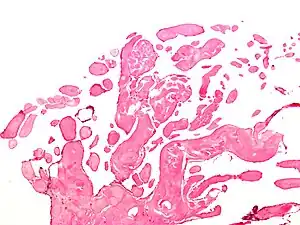

| Micrograph of a papillary fibroelastoma, a benign tumor of heart valves. H&E stain. | |

- Papillary Fibroelastoma

A subset of the primary tumors of the heart are tumors that are found on the valves of the heart. Tumors that affect the valves of the heart are found in an equal distribution among the four heart valves.[2] The vast majority of these are papillary fibroelastomas. Primary tumors of the valves of the heart are more likely to occur in males. While most primary tumors of the valves of the heart are not malignant, they are more likely to have symptoms related to the valve, including neurologic symptoms and (in a few cases) sudden cardiac death.